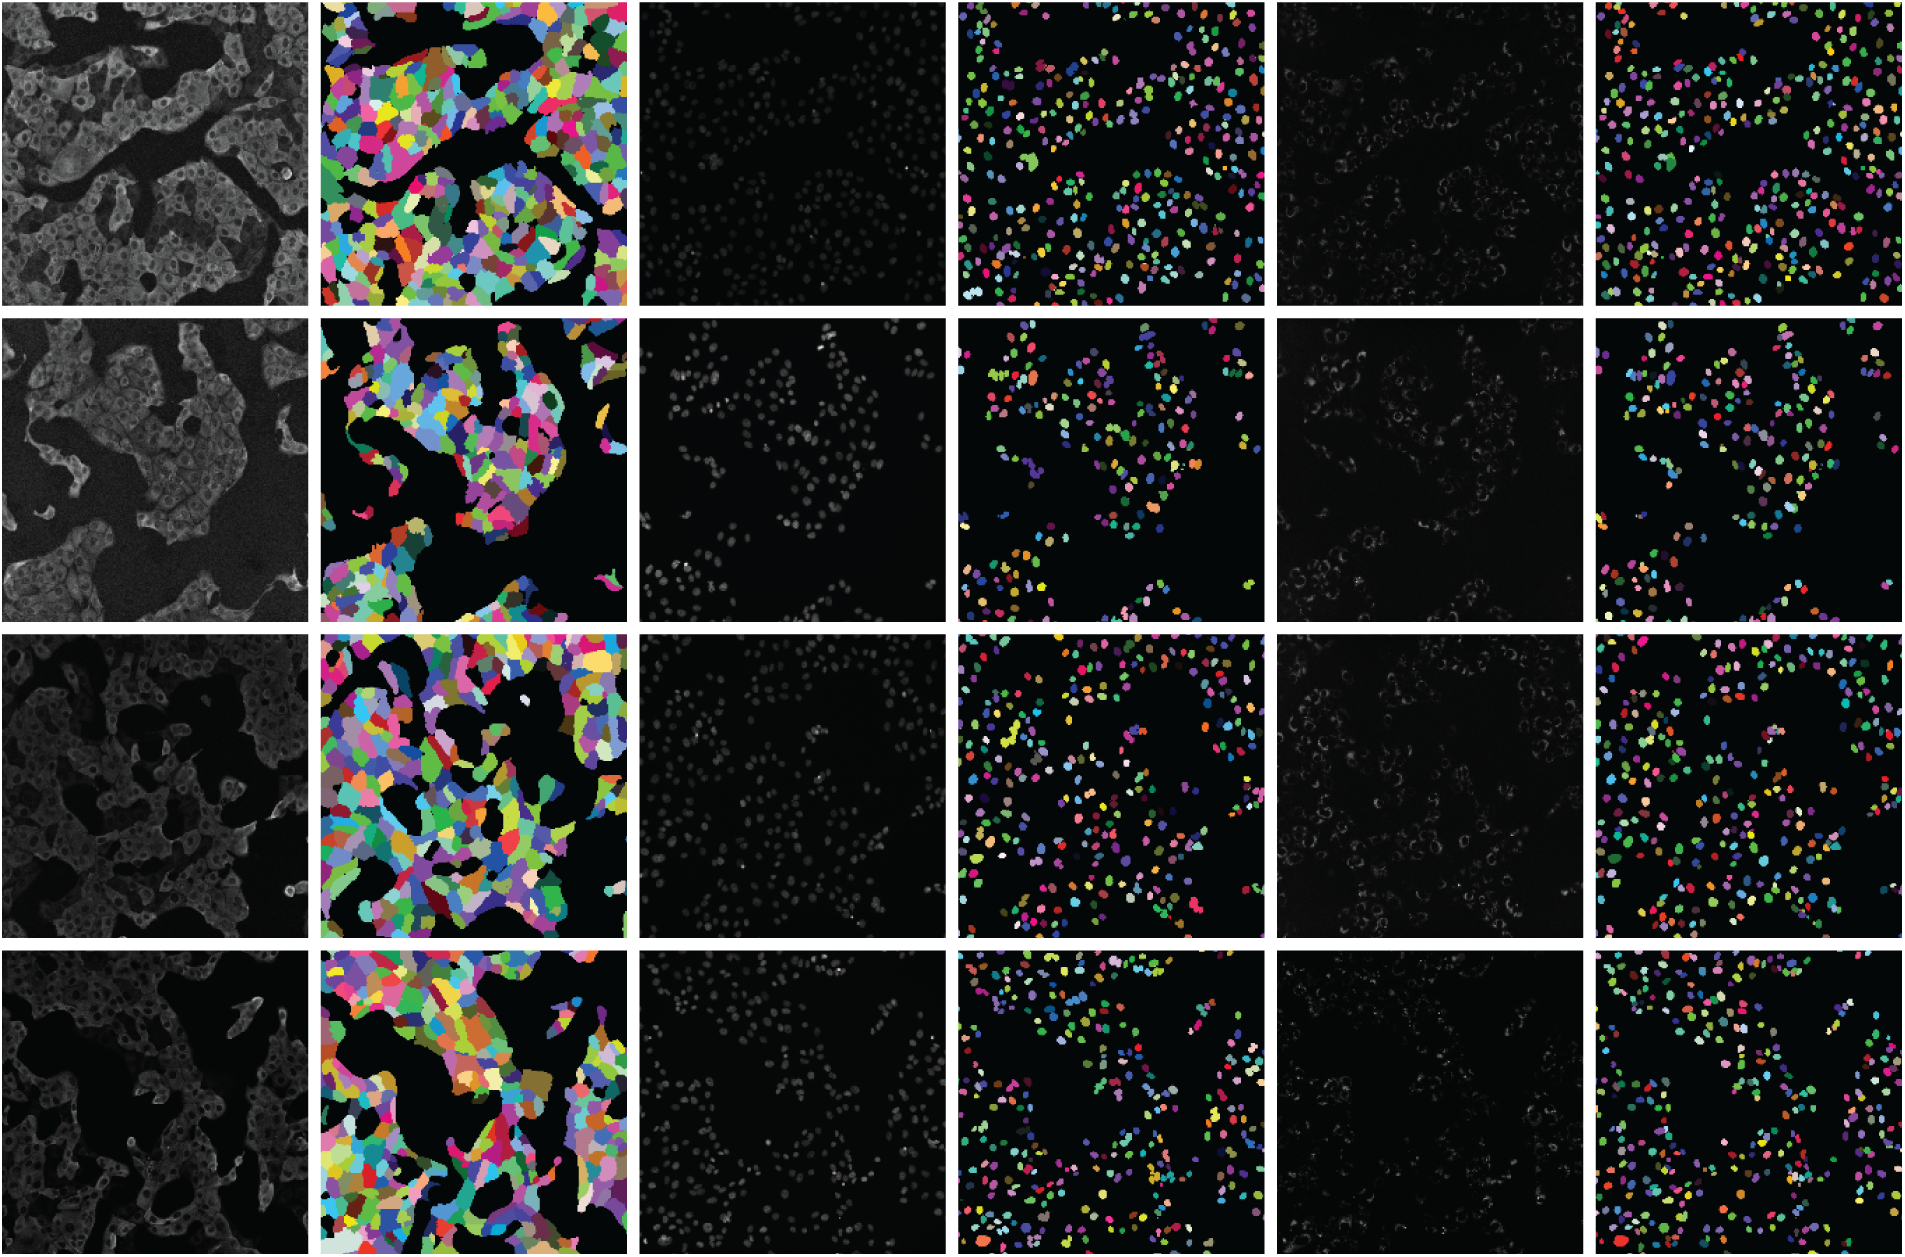

A human-in-the-loop approach was employed in [50] to annotate a large-scale dataset, wherein the outputs from a deep learning model were iteratively corrected by human experts and fed back into the model for further refinement. Multiplexed imaging plays a critical role in spatial profiling of biological components at the cellular level [103]. However, extracting meaningful information from such images requires precise instance segmentation of individual cells to enable accurate feature extraction. In this context, a deep learning model trained on a diverse dataset such as TissueNet proves highly effective. For multiplexed tissue images, instance segmentation is essential for delineating boundaries of individual cell instances. Using the TissueNet dataset, a deep learning-based model called Mesmer was developed to perform whole-cell and nuclear segmentation. Mesmer is built upon a ResNet50 [104] backbone integrated with a Feature Pyramid Network (FPN) [94], enabling it to predict both nuclear and whole-cell masks. Input images consist of two channels: one representing the nuclear signal and another corresponding to the cytoplasmic or membrane signal. These channels are normalized and processed by the model to generate spatial maps indicating centroids and boundaries of cells and nuclei. These spatial outputs serve as inputs to a watershed algorithm [105], which subsequently generates instance segmentation masks for each cell and nucleus in the image. Notably, the deep learning model does not directly output the final instance masks but rather provides spatial cues that guide the segmentation process. This approach is particularly valuable for downstream analyses, where extracted cell-level features from multiplexed images can be projected into low-dimensional spaces for phenotypic profiling and quantitative assessment of biological samples [103].

Numerous deep learning algorithms have demonstrated effectiveness in cell segmentation, but typically require substantial quantities of high-quality annotated data to achieve optimal performance. This requirement becomes particularly challenging, and costly, when annotations must delineate individual cell instances. To address the annotation burden, several studies have explored unsupervised [106] and weakly supervised learning strategies [107,108]. Unsupervised methods such as [106] have shown performance comparable to state-of-the-art approaches like CellPose [109] and Mesmer [50] in nuclei segmentation. However, their effectiveness varies across datasets, particularly when extended to broader cell segmentation tasks, varies when measured by F1 score comparisons with CellPose and Mesmer. Weakly supervised methods [107,108], though less annotation-intensive than fully supervised counterparts, still require spatial cues such as centroids or bounding boxes, which are time-consuming to generate at scale. To mitigate these challenges, the authors in [110] proposed an approach leveraging image-level segmentations alongside location-of-interest annotations for individual cells, striking a balance between annotation efficiency and segmentation accuracy.

In [110], Location Assisted Cell Segmentation System (LACSS) is introduced, a network architecture designed to balance annotation efficiency with segmentation accuracy. LACSS builds upon a Fully Convolutional Network (FCN) framework [111], employing an encoder–decoder backbone to extract hierarchical features, which are then passed to a Location Proposal Network (LPN). The LPN is tasked with predicting locations of interest (LOIs) for individual cells, though it does not estimate object sizes due to the lack of size annotations. A subsequent segmentation FCN module focuses on generating single-cell segmentations. To improve computational efficiency, segmentation is restricted to localized regions surrounding each LOI, under the assumption that distant pixels are unlikely to belong to the target cell. While LACSS is optimized for datasets with sparse or incomplete annotations, it can also be configured for fully supervised learning. In the supervised setting, the total loss comprises the LPN loss, quantifying the discrepancy between predicted and ground truth LOIs, and the segmentation loss. For weakly supervised training, the model combines LPN loss with a weak supervision objective that enforces consistency between the image-level and cell-level segmentations, enabling robust performance under limited annotation regimes.